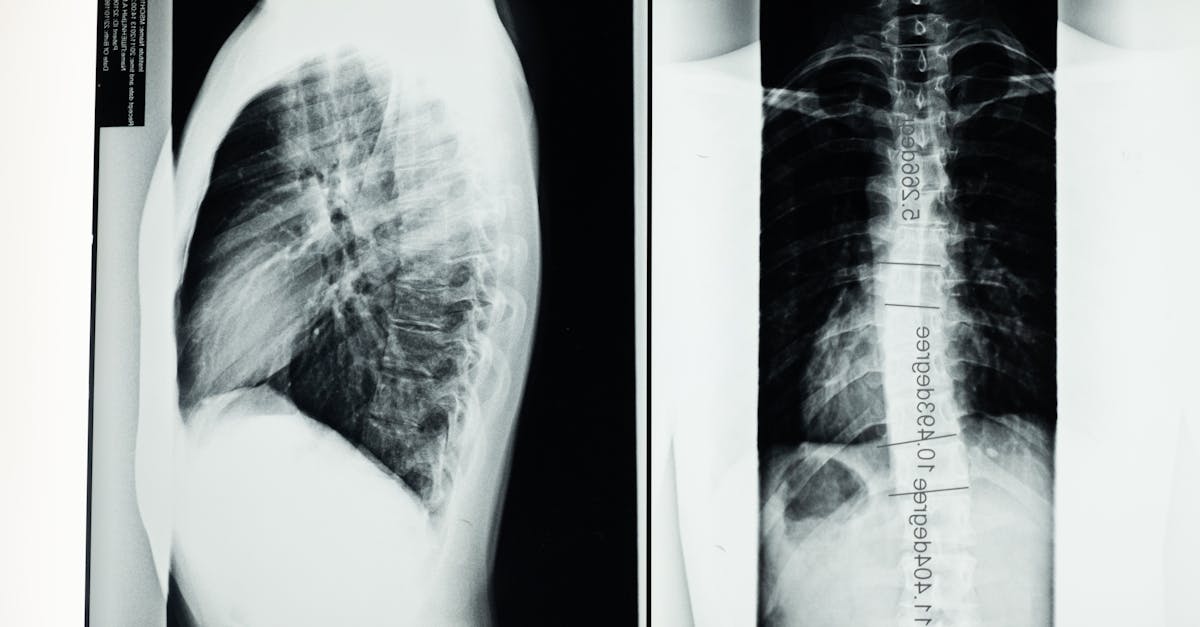

Avant de commencer un traitement par décompression neurovertébrale, il est crucial de se soumettre à une évaluation médicale complète. Les personnes âgées, en particulier, doivent être examinées en profondeur pour identifier toute condition sous-jacente qui pourrait influencer l’efficacité du traitement. Les examens d’imagerie, tels que l’IRM, peuvent être nécessaires pour évaluer l’état de la colonne vertébrale et des disques intervertébraux.